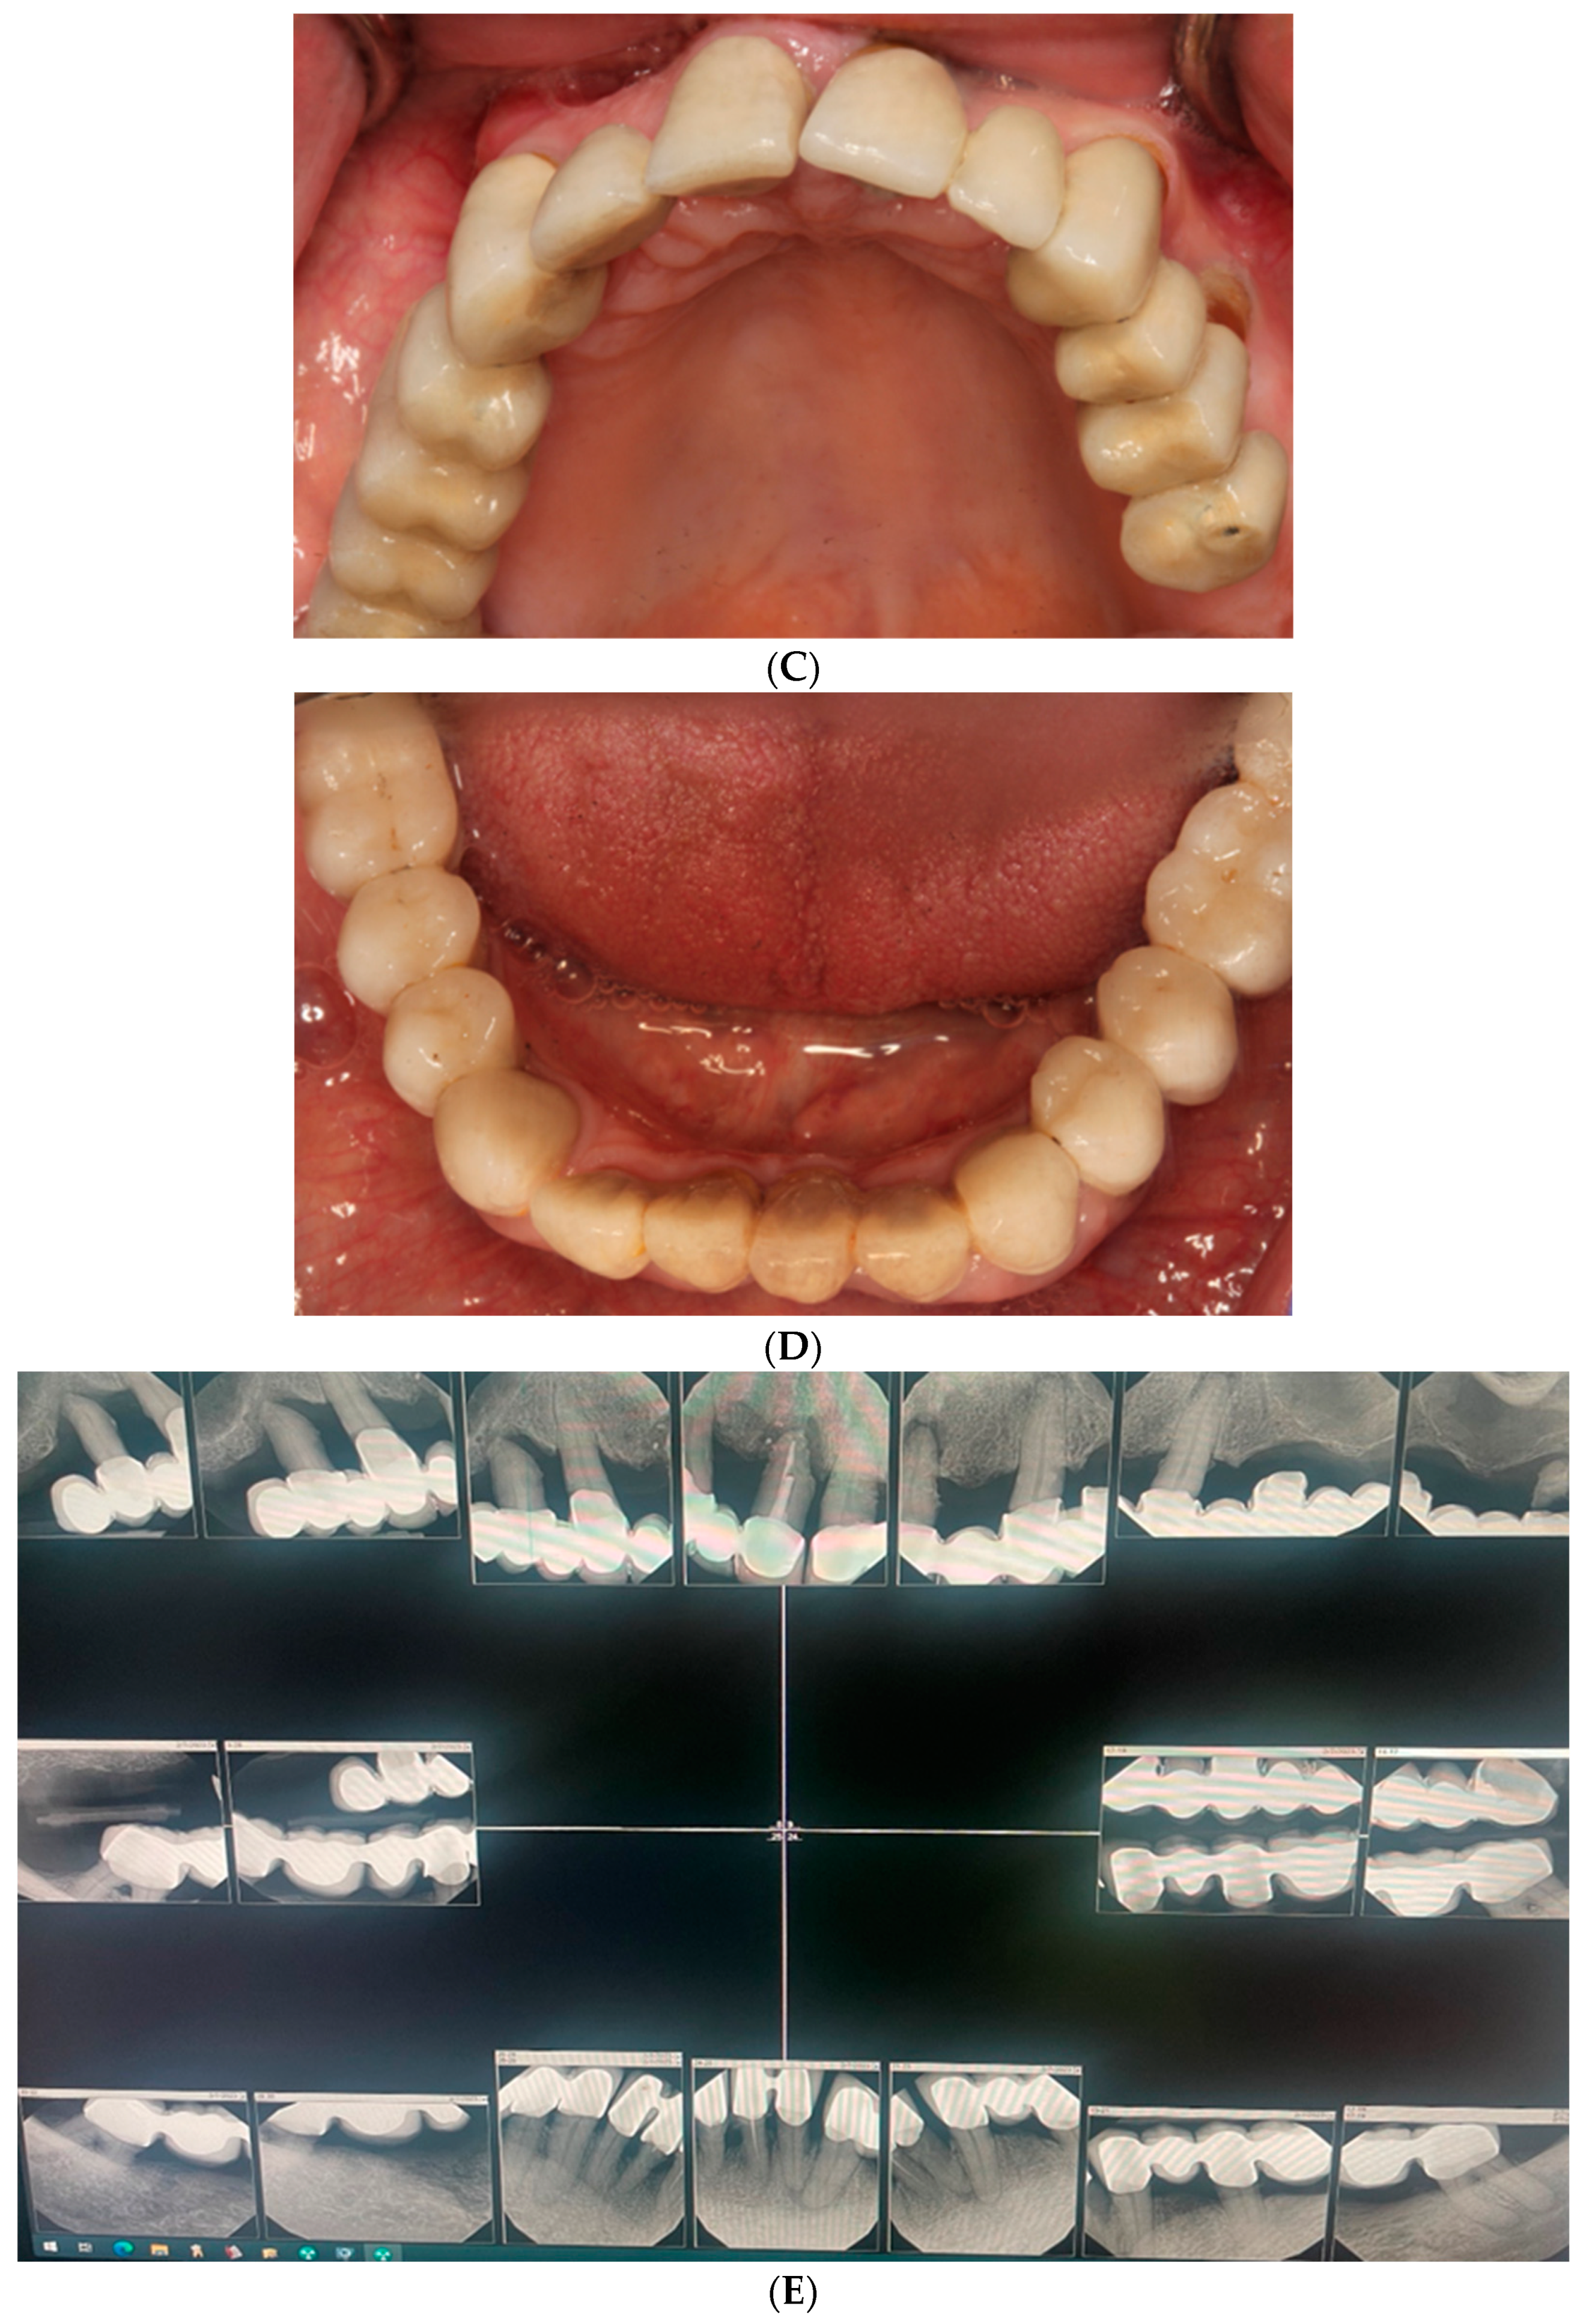

2. Case Report